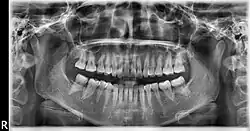

Ortopantomografía

La ortopantomografía o radiografía panorámica es una técnica radiológica que representa, en una única película, una imagen general de los maxilares, la mandíbula y los dientes. Por tanto, es de primordial utilidad en el área dentomaxilomandibular.

Su papel en el diagnóstico odontológico, no solo de los dientes sino también del maxilar y mandíbula, es fundamental. Sin la ortopantomografía, el odontólogo perdería una gran ayuda en la mayoría de las especialidades de su campo. Prácticamente, es utilizada de forma sistemática en odontología, llegando a ser un arma diagnóstica rutinaria. El valor diagnóstico de la ortopantomografía en cirugía bucal, implantología, ortodoncia, periodoncia y en patología oral y dental está claramente demostrado.

El término de radiografía panorámica es el más comúnmente utilizado, ya que la radiografía resultante muestra una visión panorámica de la cara y parte inferior de la cabeza. Laudenback describe la ortopantomografía como uno de los inventos radiológicos más originales de los últimos decenios. El 40 % de los hallazgos patológicos principales y secundarios se descubren a partir de ella. Amplía el campo de diagnóstico en un 70 % y reduce la dosis de radiación de la superficie cutánea en un 90 % con respecto a las series radiográficas periapicales.